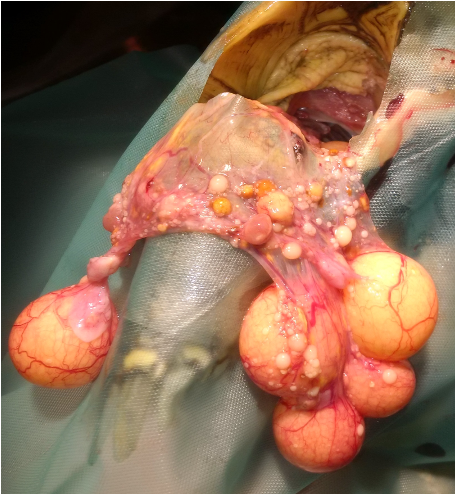

Stase folliculaire

Troubles de l’ovulation pré-ovulatoire : diagnostic échographique et chirurgie.